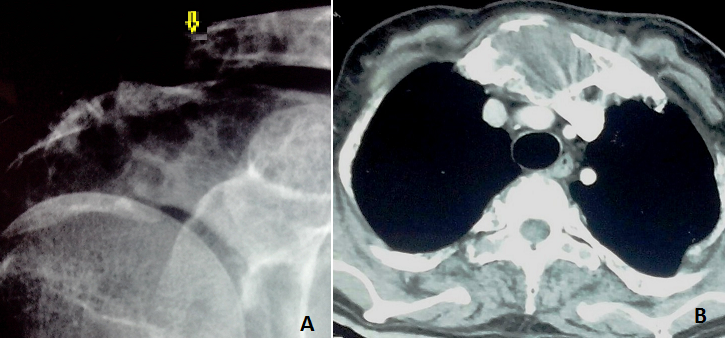

Un homme de 46 ans, sans antécédents pathologiques notables, est hospitalisé pour une altération de l'état général avec troubles de la marche évoluant depuis 6 mois. On constate à l'examen physique des ecchymoses périorbitaires droites et une tuméfaction de l'extrémité interne de la clavicule droite et du sternum. L'imagerie standard ainsi que la tomodensitométrie thoraco-abdominale révèle un aspect hétérogène diffus à toute la trame osseuse avec une fracture pathologique de l'extrémité externe de la clavicule (A) et une masse lytique sternale (B) dont la biopsie conclu à la présence de dépôts amyloïdes. On notait par ailleurs à la biologie une hypercalcémie à 2,8 mmol/l et une anémie normochrome normocytaire à 10 g/l. L'électrophorèse des protides était normale et le myélogramme ne montre pas d'infiltration lympho-plasmocytaire. A La biopsie ostéomédullaire on note la présence d'une amylose médullaire et à l'échographie cardiaque, un aspect infiltré tigré du myocarde, un trouble restrictif et une lame d'épanchement péricardique. L'évolution était rapidement fatale avant le typage de l'amylose. La localisation osseuse de l'amylose, révélatrice chez ce patient, est rare. Elle réalise un tableau clinique de tuméfaction osseuse ou de fracture pathologique avec atteinte essentiellement vertébrale. Le principal diagnostic différentiel est celui de lésion tumorale maligne primitive ou secondaire.